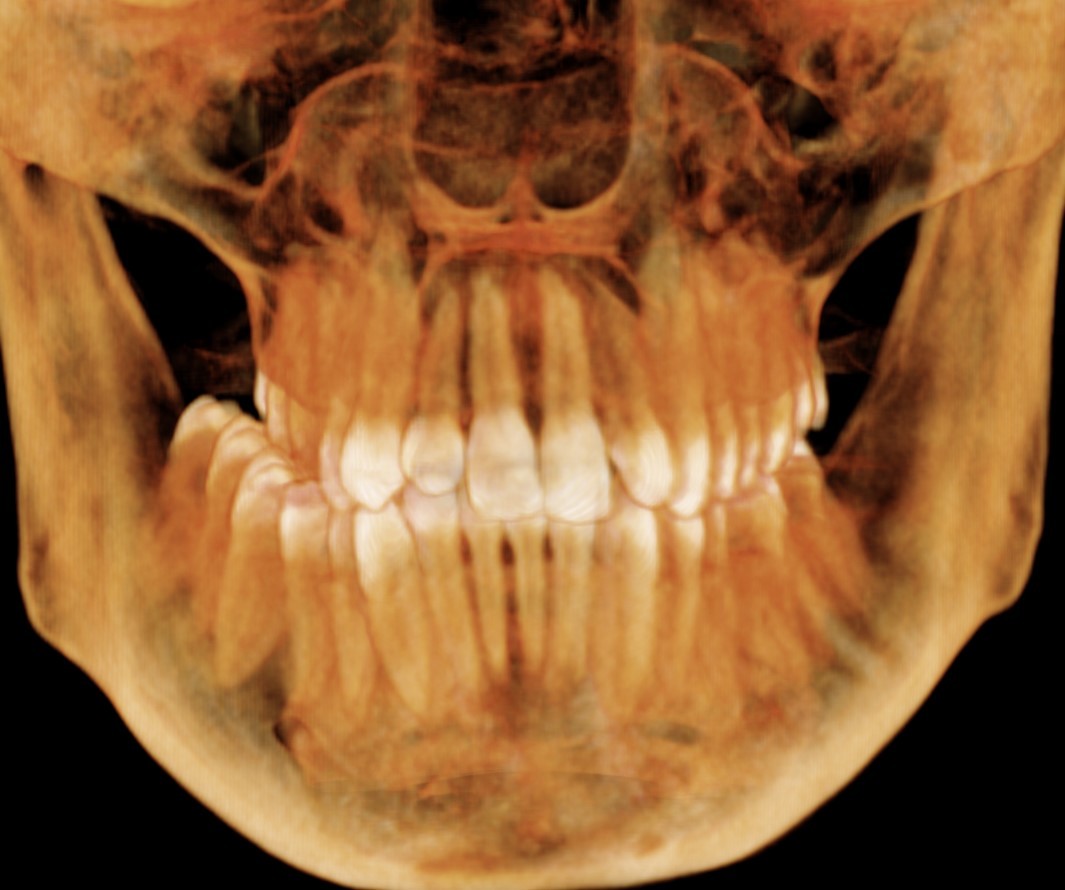

Przekrój szczęki rok po leczeniu.

Rok po ekspansji - prawidłowy zgryz, proste zęby.